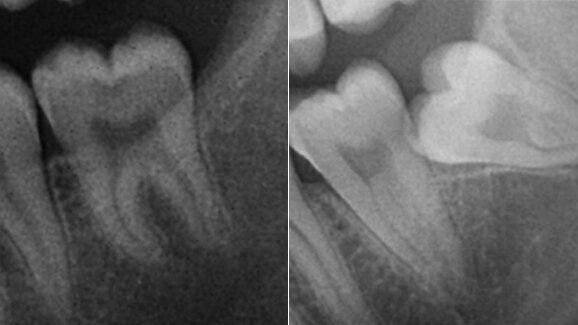

A presurgical radiographic scale was developed, based on ten parameters. Each parameter was scored from 1 to 3, and the individual scores were summed. A retrospective analysis using panoramic radiographs was performed of patients subjected to surgical extraction of a mandibular third molar, with recording of the surgical times. A statistical analysis was performed to establish correlations between the study parameters and scale and the surgical times.

A greater Winter’s distance prolonged ostectomy time and, conversely, a greater distance from the mandibular ramus to the distal surface of the second molar was observed to shorten ostectomy time. Separate or dysmorphic root shape increased ostectomy time and total surgical time. Total surgical time was longer in the presence of greater coronal width and a shorter distance from the ramus to the second molar. The only variable correlated to tooth sectioning time was coronal width.

The final score was correlated to ostectomy time and total surgical time. Ostectomy time in turn was influenced by Winter’s distance, the distance from the mandibular ramus to the second molar, and root shape. Tooth sectioning time was influenced by the coronal width of the third molar. The parameters with the closest correlation to total surgical time were coronal width and the distance between the ramus and second molar.